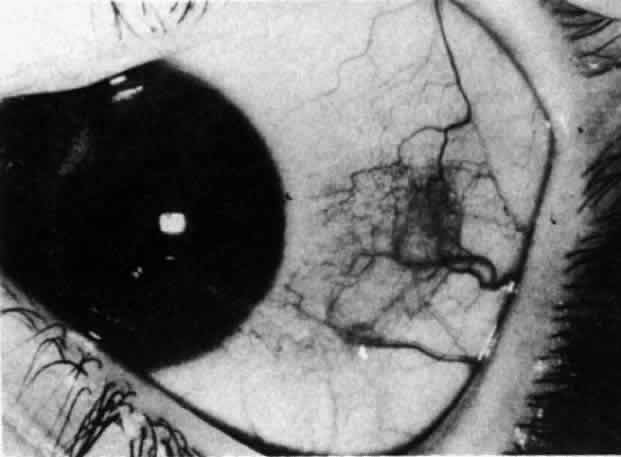

The redness of simple episcleritis may be intense, varying from a fiery-red or a brick-red discoloration to a mild red flush, but it does not have the bluish tinge that is seen in scleritis. The distribution is usually sectorial but can involve the whole anterior segment of the globe. The episcleral vessels are engorged but retain their normal radial position and architecture (Figs. 13 and 14; Color Plate 1A). In simple episcleritis, there is a diffuse edema of the episcleral tissues. These tissues are sometimes infiltrated with gray deposits that appear yellow in red-free light. Surprisingly, the eye is rarely tender to the touch.

The inflammation of the eye is a prominent feature. The inflammation has a bluish-red hue in contrast to the brighter red of episcleritis and may be sectorial or diffuse. The severity of inflammation seems to depend on the amount of episcleral tissue present. Therefore, it is more prominent in younger people and is least prominent in those with rheumatoid arthritis in whom the episcleral tissue almost disappears.

Each of the various types of scleritis can be distinguished by its typical clinical appearance. Because the pathologic change is in the sclera, there is always edema and/or necrosis of that tissue. This gives rise to an overlying episcleral edema and to congestion that may be very severe and may need blanching with epinephrine 1:1000 or phenylephrine 10% to detect the underlying edema.

The sclera that is edematous is pushed forward, and the deep episcleral network is more congested than the superficial networks (Figs. 27 and 28). It is usually easy to ascertain by simple observation that the patient has scleritis and not episcleritis. However, it is not as easy to ascertain whether the patient has early necrotizing scleritis. It is in these patients that fluorescein angiography has considerable value, because the first changes are detectable in the ocular vasculature. Prompt and adequate treatment can prevent these changes from becoming irreversible.